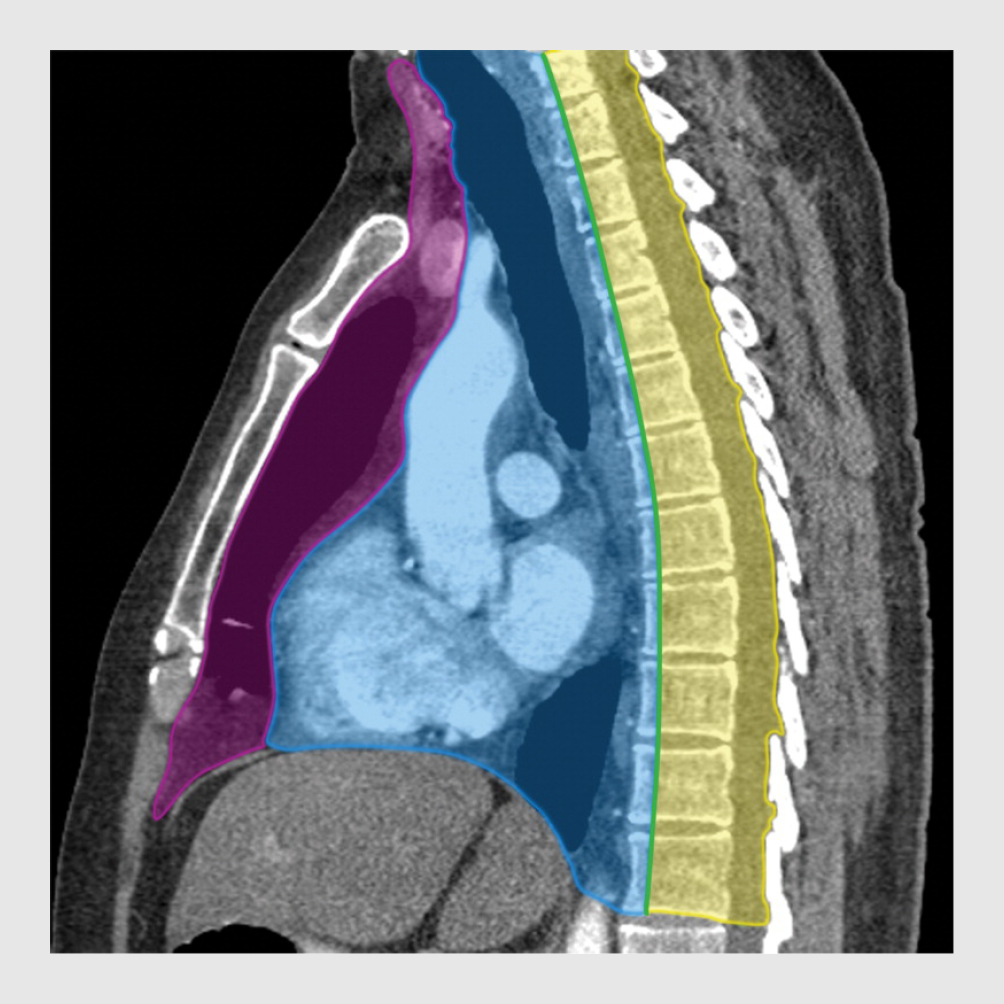

Aldaar werd een benauwd meisje gezien die in korte zinnen sprak. Er was sprake van neusvleugelen, orthopneu en oedeemvorming in het gelaat. De halsvaten waren gestuwd. Bij lichamelijk onderzoek palpeerde de anios kindergeneeskunde fors vergrote cervicale en supraclaviculaire lymfeklieren. Bij auscultatie van de longen hoorde zij bronchiaal en rechts basaal ook verminderd ademgeruis. De lever was 3 cm onder de ribbenboog palpabel. Omdat de zuurstofsaturatie daalde naar 93%, kreeg patiënte zuurstof toegediend. De röntgenfoto van de thorax toonde een fors verbreed mediastinum, waarschijnlijk veroorzaakt door een lymfadenopathie. De trachea was naar rechts verplaatst en beiderzijds was pleuravocht zichtbaar (figuur 1).

Figuur 1

Figuur 1 |

Anterieur-posterieure röntgenopname van de thorax van een 16-jarige meisje in zittende houding. De opname toont een verbreed mediastinum, een naar rechts verplaatste trachea en beiderzijds pleuravocht.